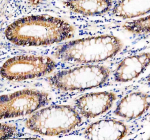

IHC analysis of UBE2A/UBE2B using anti-UBE2A/UBE2B antibody. UBE2A/UBE2B was detected in a paraffin-embedded section of human colon tissue. Heat mediated antigen retrieval was performed in EDTA buffer (pH 8.0, epitope retrieval solution). The tissue section was blocked with 10% goat serum. The tissue section was then incubated with 2 ug/ml rabbit anti-UBE2A/UBE2B antibody overnight at 4oC. Peroxidase Conjugated Goat Anti-rabbit IgG was used as secondary antibody and incubated for 30 minutes at 37oC. The tissue section was developed using an HRP secondary and DAB substrate.